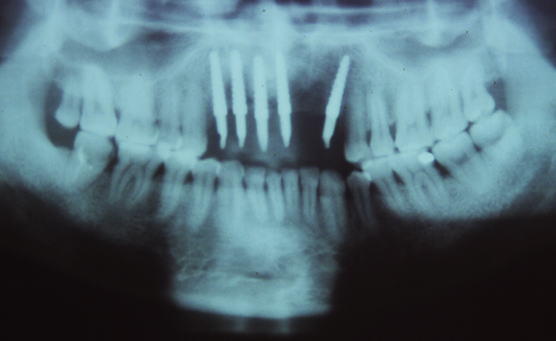

症例101